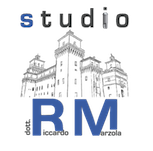

1. La quantità di osso tra il punto A ed il punto B non è sufficiente per inserire un impianto di dimensioni adeguate. |